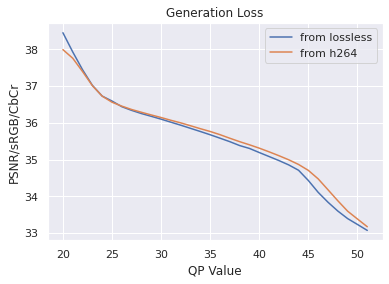

Data: As in [9], our colonoscopy video dataset was collected from screening colonoscopy procedures performed in three hospitals. We used a detector trained on a 16K video subset of the dataset, and we computed our classical codec analyses on a different 80 video subset (2.2M frames, 15K polyp frames). All videos and metadata were deidentified according to the Health Insurance Portability and Accountability Act Safe Harbor. Ground truth polyp labeling was provided by the gastroenterologist annotators described in [9]. The annotators were paid on an hourly basis, and pay was not based on the results they provided. The videos were compressed using H264 QP20 when transmitted from the hospitals. To justify our analyzing already-compressed videos, we used a small number of lossless videos to investigate the impact of re-compressing compressed videos to QP (so called “generation loss"). We found that the impact was negligible (see Appendix for details).

Since our dataset was compressed to be transferred from hospitals, we first investigated the impact of multiple stages of compression ("generation loss"). We used lossless video (24 seconds, 1.4GB) collected from an endoscope viewing dyed, non-human tissue. This gave the video the motion and texture characteristics of a colonoscopy. We then compared video quality between two compression schemes: compressing using H264 QP , where , and compressing to H264 QP20, then to H264 QP (when referring explicitly to this comparison, we will concisely refer to the latter as ’QP’). We then compared the average frame quality between these two schemes using two quality metrics (see ’Metrics’ section). The quality differences between these two compression schemes was minor in terms of PSNR-CbCr, which justifies our working with video data already compressed by H264 QP20.